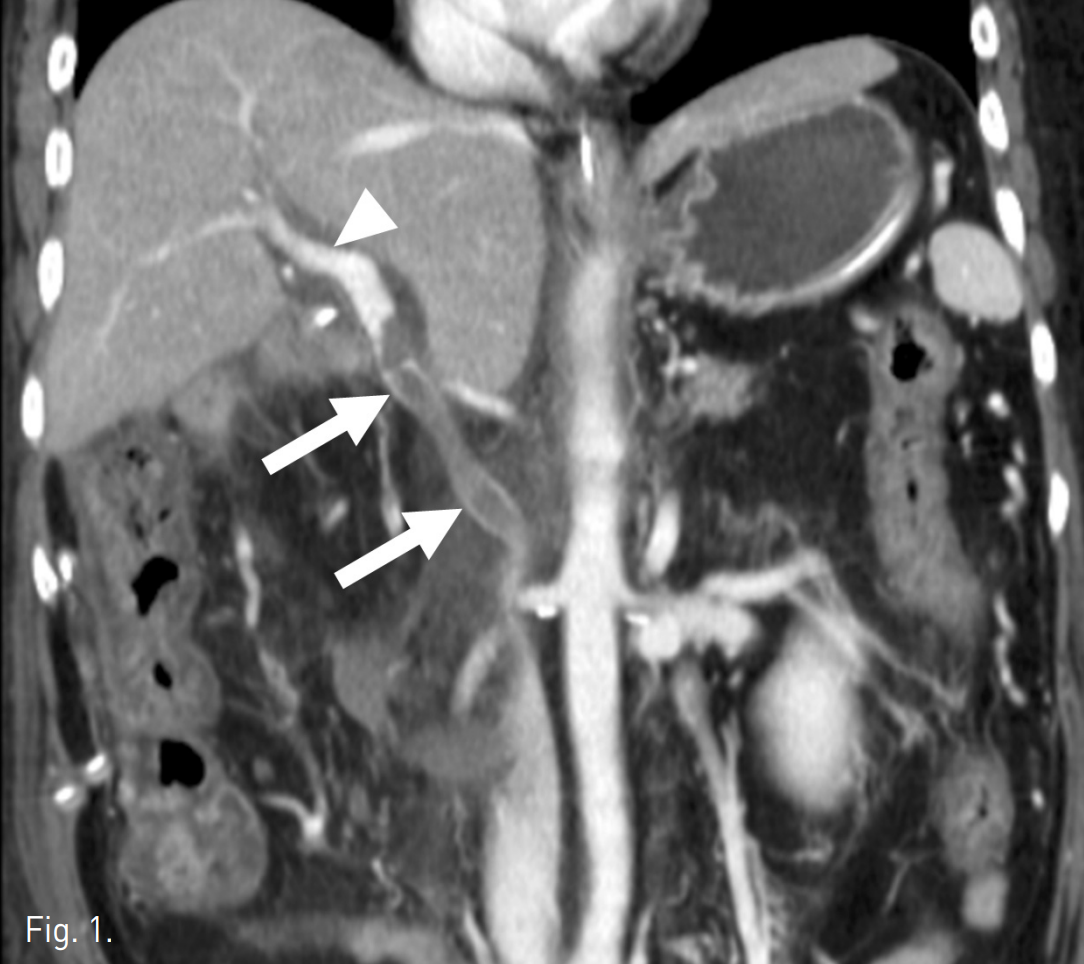

초음파 유도 하에서 우측 문맥을 20G Chiba needle을 이용해 직접 천자한 후 문맥 조영 영상에서 문맥부 합성혈관의 혈전성 폐색을 확인하였다(Fig. 2A). 5F Davis catheter (Cook, Bloomington, IN, USA)와 urokinase (200K unit)를 이용한 혈전용해술, 7F Sheath catheter (Cook, Bloomington, IN,USA)를 이용한 흡입 혈전제거술과 stent를 이용한 치료를 계획하였다. 혈전용해술 및 흡입 혈전제거술을 시행한 후 문맥의 혈류가 회복되었으나 이 과정에서 간 내 문맥(intrahepatic portal vein)에 혈전성 색전에 의한 것으로 보이는 간 내 문맥의 충만결손이 발생하였고(Fig. 2B), 이에 대해 다시 흡입혈전제거술을 시행하여 문맥의 흐름을 원활히 하였다. 이후 자가팽창형 스텐트(10mm x 80mm)(S&G biotech, Seoul, Korea)를 합성혈관의 근위부 및 원위부 접합부를 모두 포함하도록 설치하였다(Fig. 2C), 스텐트를 위치시킨 후 시행한 문맥조영술에서 간 내 문맥의 충만결손이 사라지고 스텐트 삽입 부위의 문맥의 혈류가 원활하며 출혈 등의 시술 후 부작용이 없음을 확인하고 시술을 종료하였다 (Fig. 2D).

Fig. 2

C. Self expandable stent (10mm x 80cm) was deployed to cover the proximal and distal anastomotic stenosis. Before the stent deployment, aspiration thrombectomy was done for an embolic thrombus in the in trahepatic por tal vein.